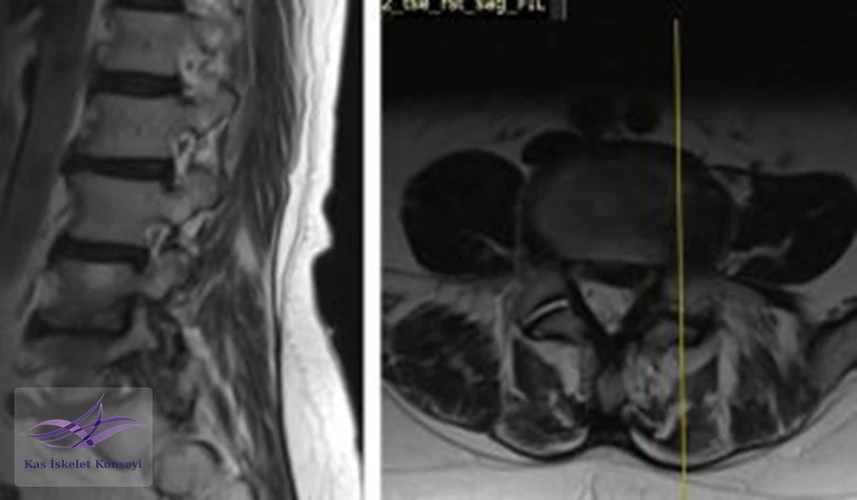

İncelemeler: Lomber MRG: L4-5 diskal bulging ve sol foraminal stenoz var. Kalça MRG istendi, iki yanlı trokanterik bursit rapor edildi.

Resim 2. Lomber MRG, L4-5 seviyesi sağ paramedian kesit.

Resim 3. Lomber MRG, L4-5 seviyesi sol paramedian kesit foramen stenozunu göstermekte.